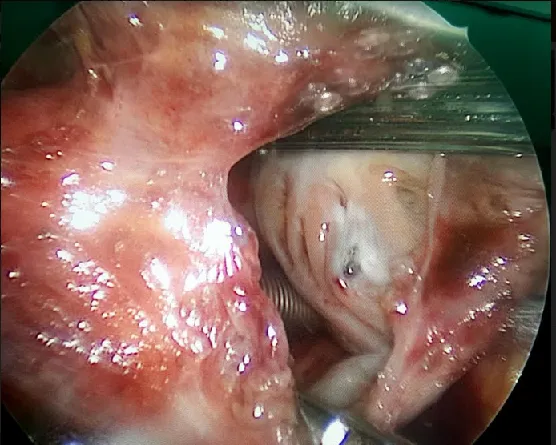

Các dị vật được gắp ra qua ngã nội soi

Sau khi chẩn đoán hình ảnh qua MRI, các bác sĩ phát hiện dị vật nằm sau nhãn cầu mắt trái của bệnh nhân rất khó lấy ra, mà nếu không lấy thì mắt sẽ áp xe có thể gây mù mắt